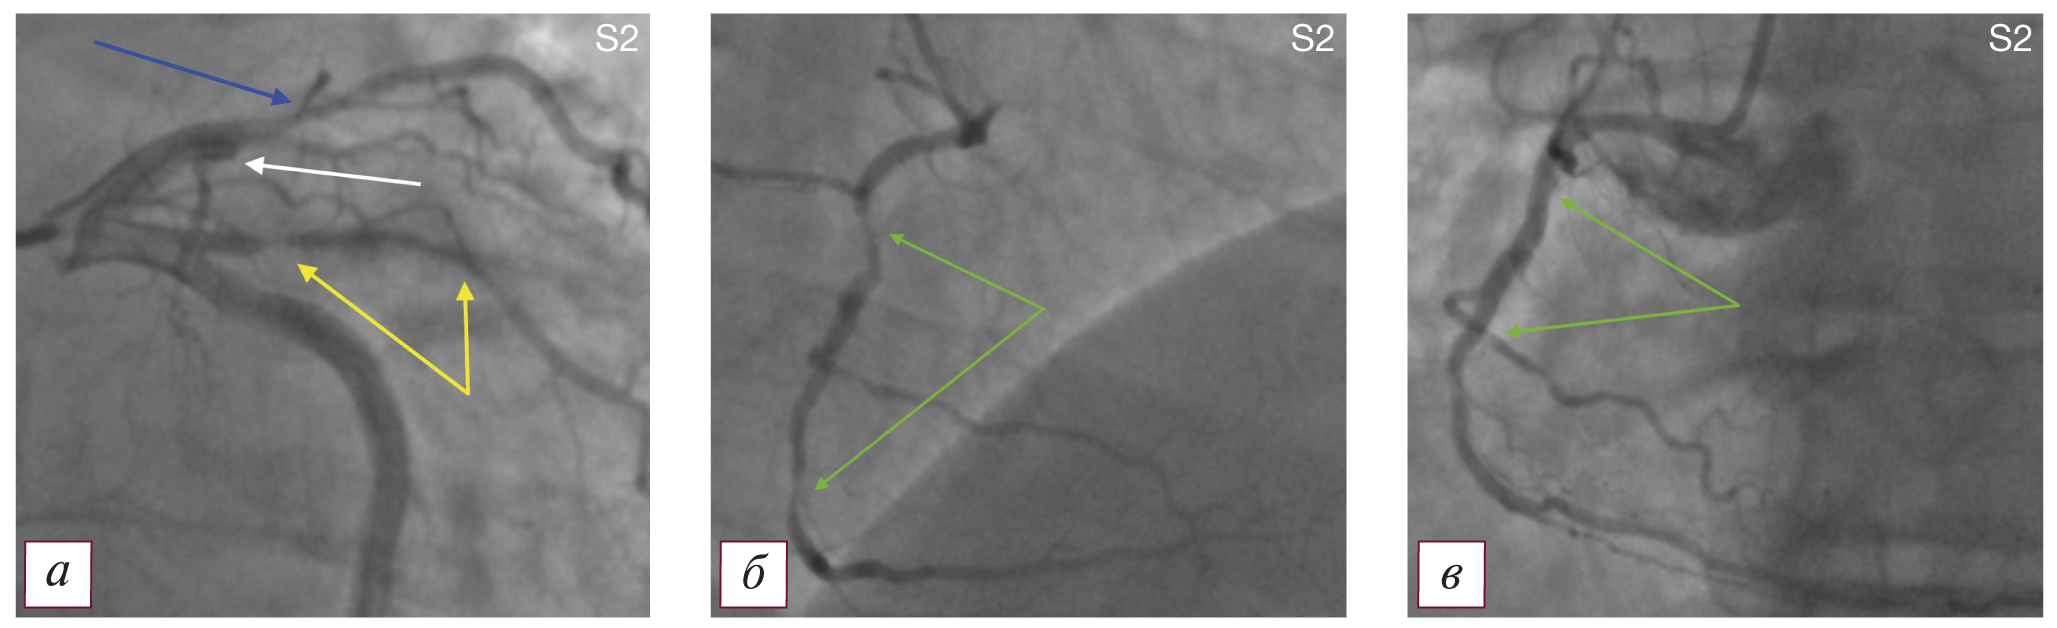

Тип S2 — ПАЛЖ и гемодинамически значимое поражение проксимальной части правой коронарной артерии с нарушением ритма ишемического генеза при левом типе кровоснабжения миокарда (рис. 4).

Рис. 4. Коронароангиографическая картина поражения коронарного русла и постинфарктной аневризмы левого желудочка по типу S2: а — окклюзия передней нисходящей артерии в проксимальной трети (белая стрелка), стеноз 1-й диагональной артерии в проксимальном сегменте 70% (синяя стрелка), субокклюзия интермедианной артерии в проксимальном сегменте (желтые стрелки); б — гемодинамически значимые стенозы на границе проксимальной и средней трети (90%), а также средней и дистальной трети (85%) правой коронарной артерии (зеленые стрелки); в — правая коронарная артерия после стентирования (зоны стентирования указаны зелеными стрелками). / Fig. 4. Coronary angiographic picture of the lesion of the coronary bed and postinfarction aneurysm of the left ventricle type S2: а — occlusion of the anterior descending artery in the proximal third (white arrow), stenosis of the 1st diagonal artery in the proximal segment 70% (blue arrow), subocclusion of the intermediate artery in the proximal segment (yellow arrows); б — hemodynamically significant stenoses at the border of the proximal and middle thirds ( 90%), as well as the middle and distal third (85%) of the right coronary artery (green arrows); в — the right coronary artery after stenting (stenting zones are indicated by green arrows).